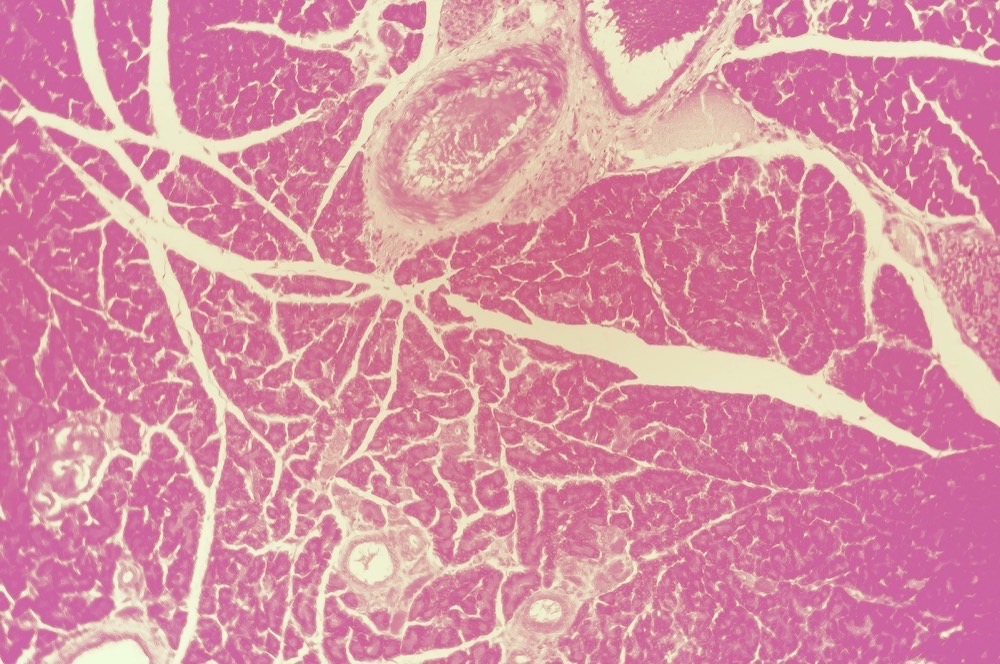

Nearly every creature with a backbone has a pancreas, lungfish and lamprey eels and ray-finned fishes being notable exceptions. In mammals, the organ is always small, shown in anatomical drawings peeping from behind the stomach or duodenum of the lion, the rabbit, the chimpanzee: red in dogs, brown or green in frogs, pinkish tan in humans. The human pancreas looks like a fleshy leaf, like an ornament on a gilded painting offering glory to the gods. It reclines between duodenum and spleen, linked to both by elegant, fragile tubes, silent and unassuming until something goes awry.

Dr. Oddi, a late-nineteenth-century Italian physiologist—who dissected cats, chickens, dogs, humans, oxen, pigeons, pigs, and sheep, so he could draw their organs—compared the texture of the pancreas to raw silk. He became a depressive cocaine addict and was eventually tried in a court of law for killing one of his patients through overmedication. His name lives on as a pancreatic duct.

In a children’s book about how we die, translating frightful ideas for fresh young minds, I found a photograph of a human pancreas cell. It is gorgeously ugly, hideously beautiful: crimson globes embedded in a pinkish-tan oval, all nestled on a bed of cabbage-olive green, spun through with gossamer gold.